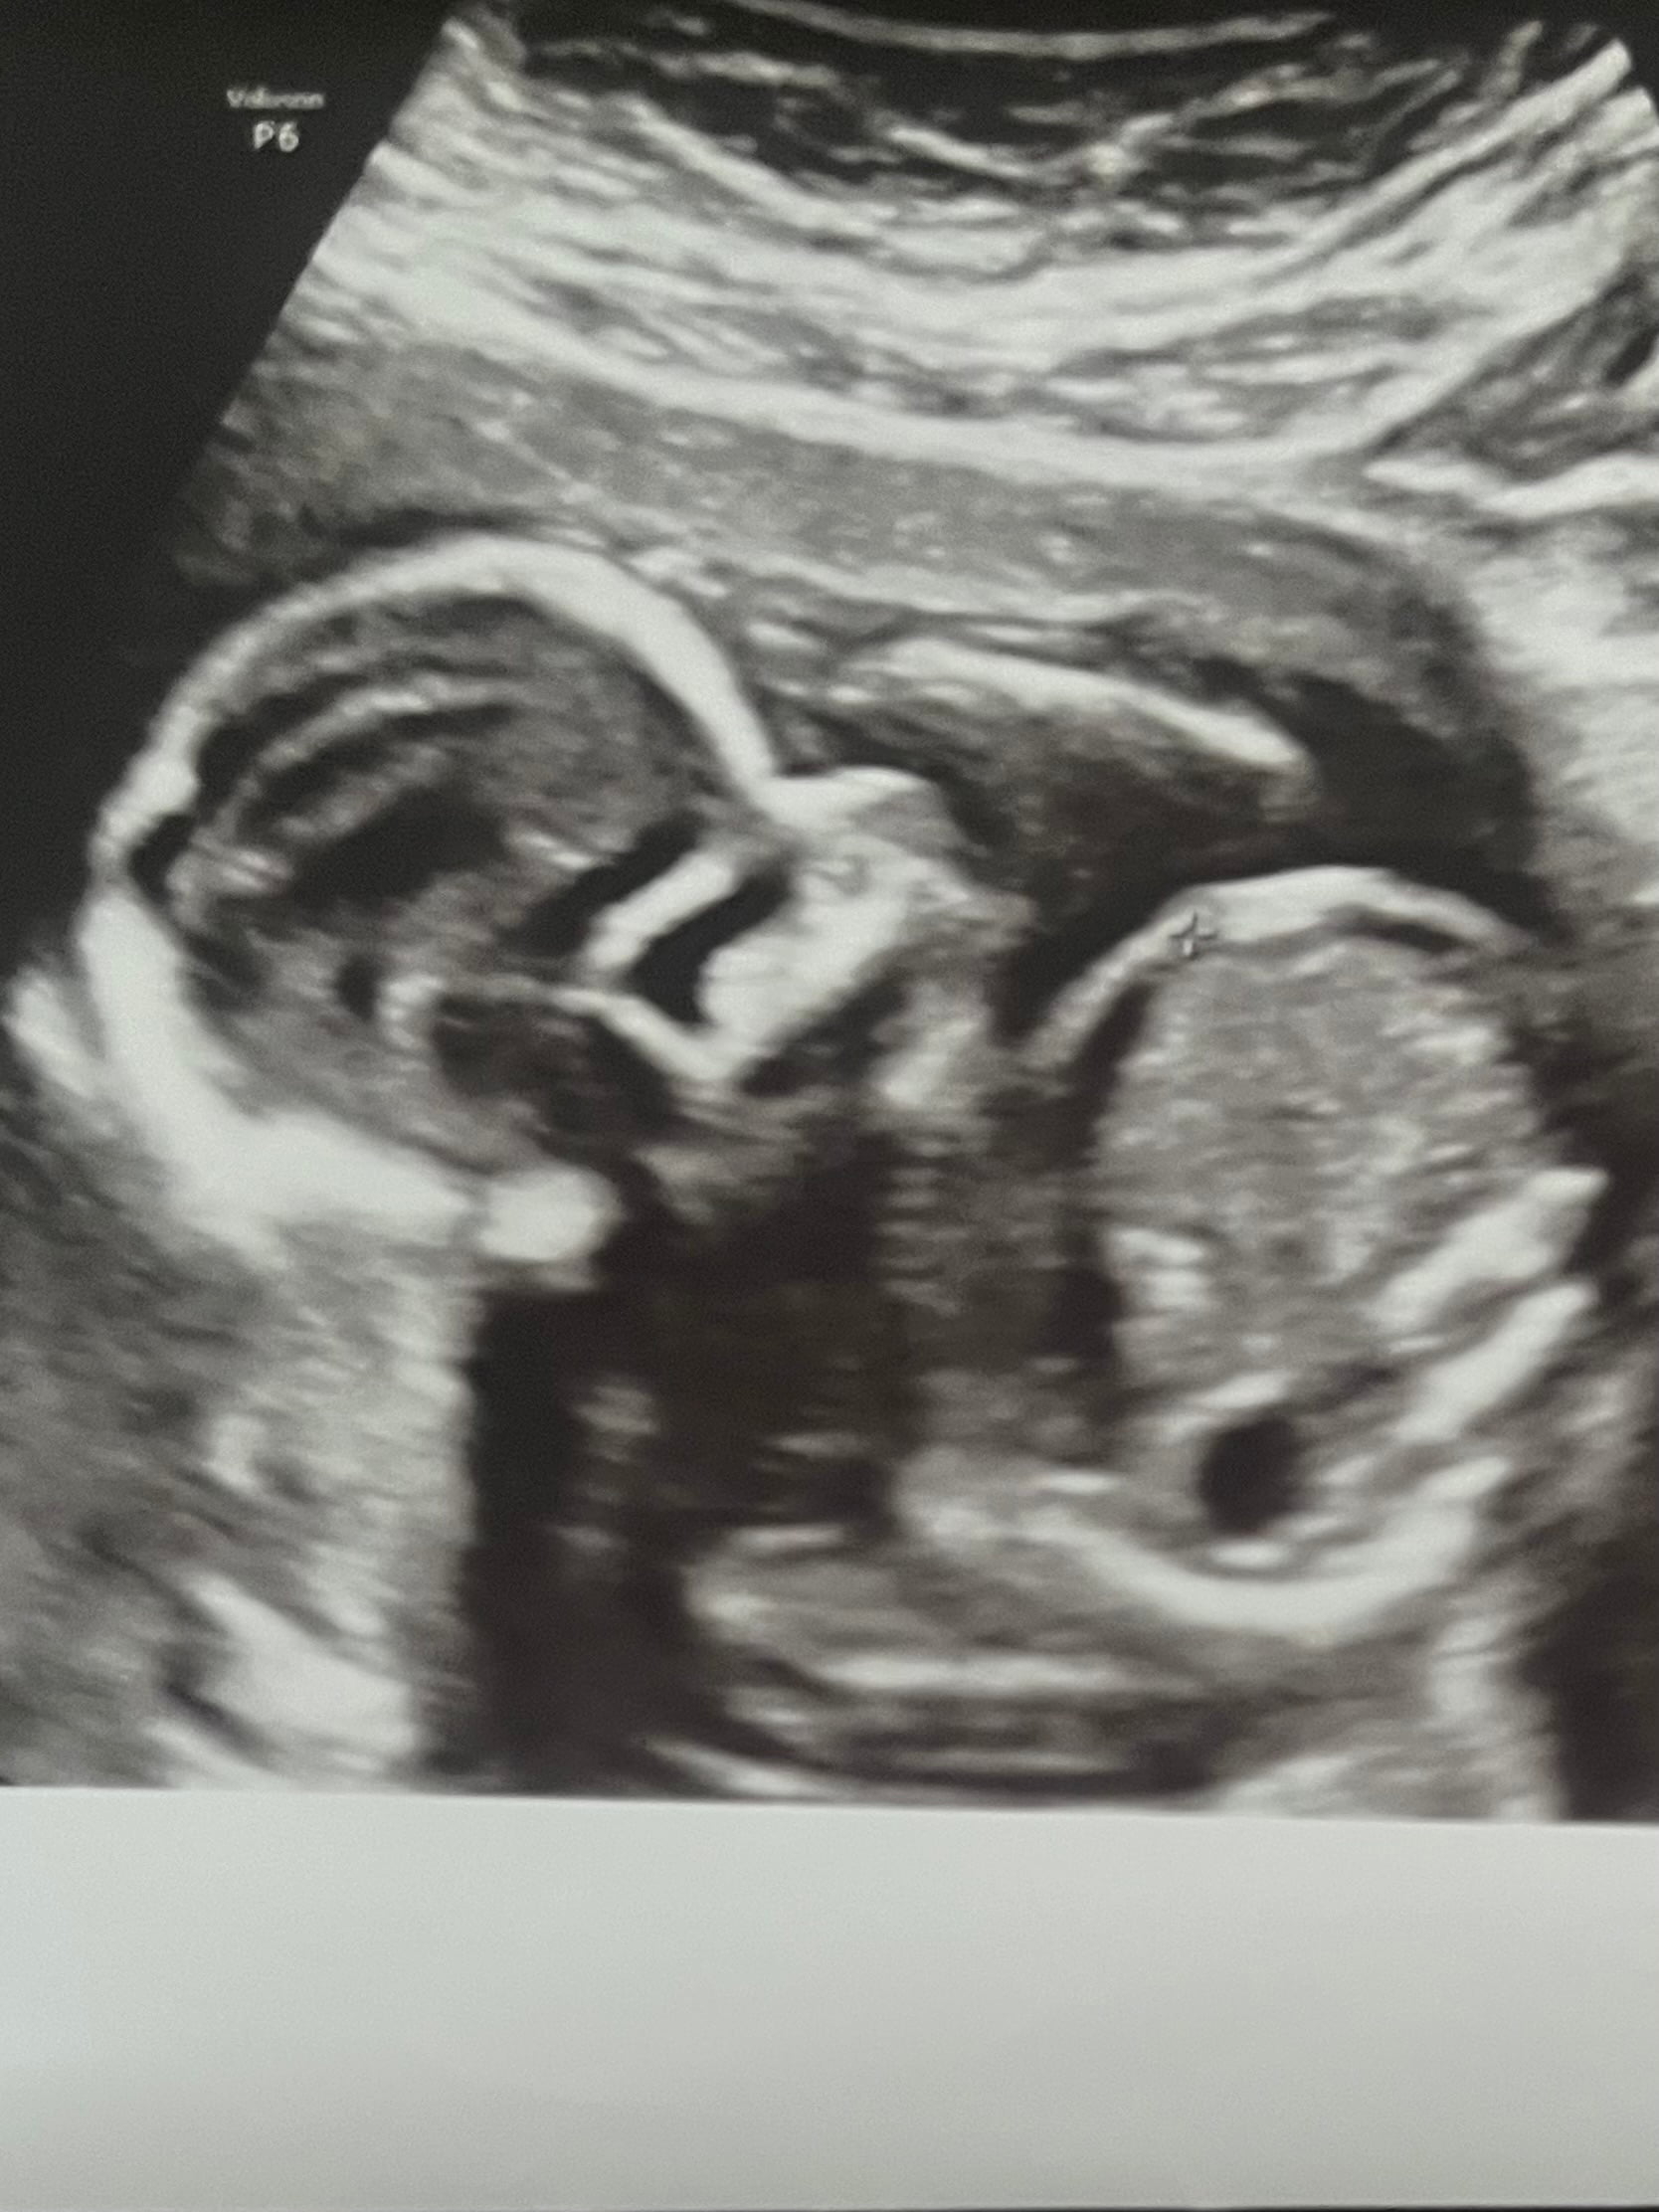

Ben şansımı baya zorlamaya çalışıyorum. Sanırım tam cinsiyet öğrenene kadar her gitmemde sana foto ayıcam gibi ![]()

Ben de seve seve yorumlarim![]()